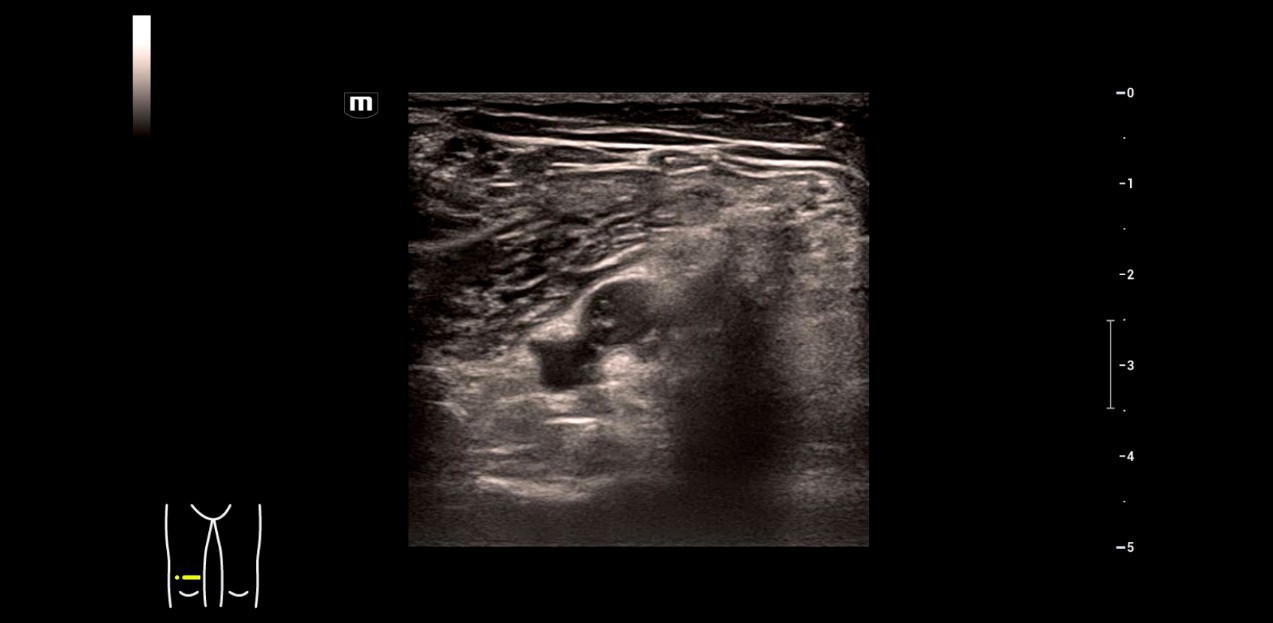

2. Severe mitral insufficiency with tearing of the support apparatus of the posterior valve segment.